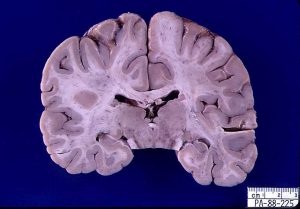

尽管有这些障碍,但一些病毒仍然可以感染大脑。当发生这种情况时,它们经常会导致致命疾病。Wiley教授审查了出苗的病毒感染和他们在过去的50年里造成的神经病理学。这里有一些例子。

Wiley教授审查了出苗的病毒感染和它们在过去50年中引起的神经病理学。